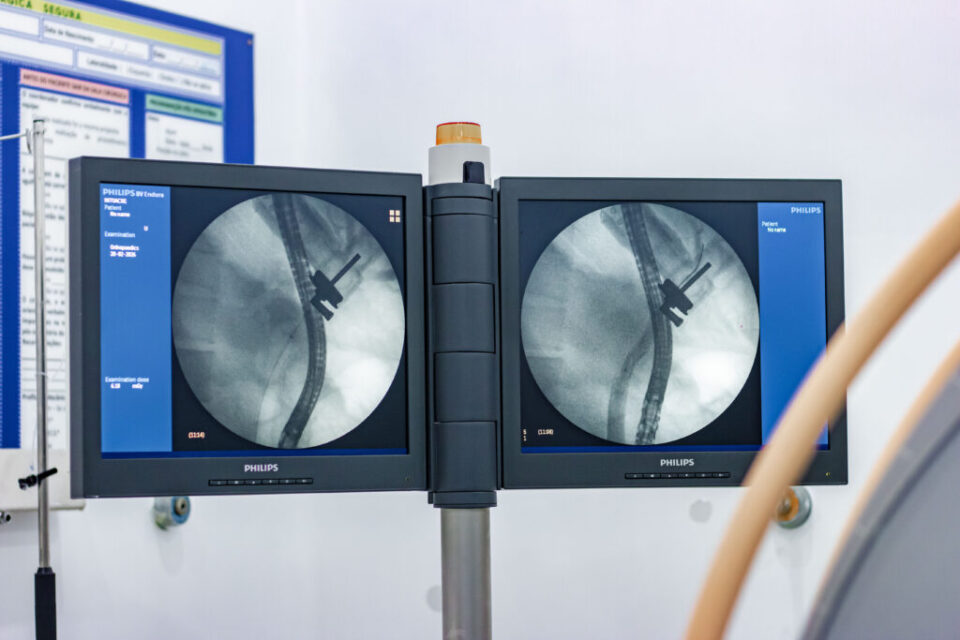

Trata-se de uma técnica complexa, que combina endoscopia e radiologia. Segundo o médico cirurgião Ian Hernandes, a ferramenta é essencial quando há obstruções nos canais que levam a bile ao intestino. “A CPRE possui indicações específicas. A principal delas ocorre quando a pedra da vesícula se desloca e vai para um canal chamado colédoco, causando complicações. Nesses casos, realizamos o exame que, além de confirmar o diagnóstico, possibilita o tratamento no mesmo procedimento. O paciente dá entrada, realizamos a CPRE e, geralmente, ele permanece cerca de 24 horas na unidade, sob todos os cuidados da equipe”, explicou Hernandes.